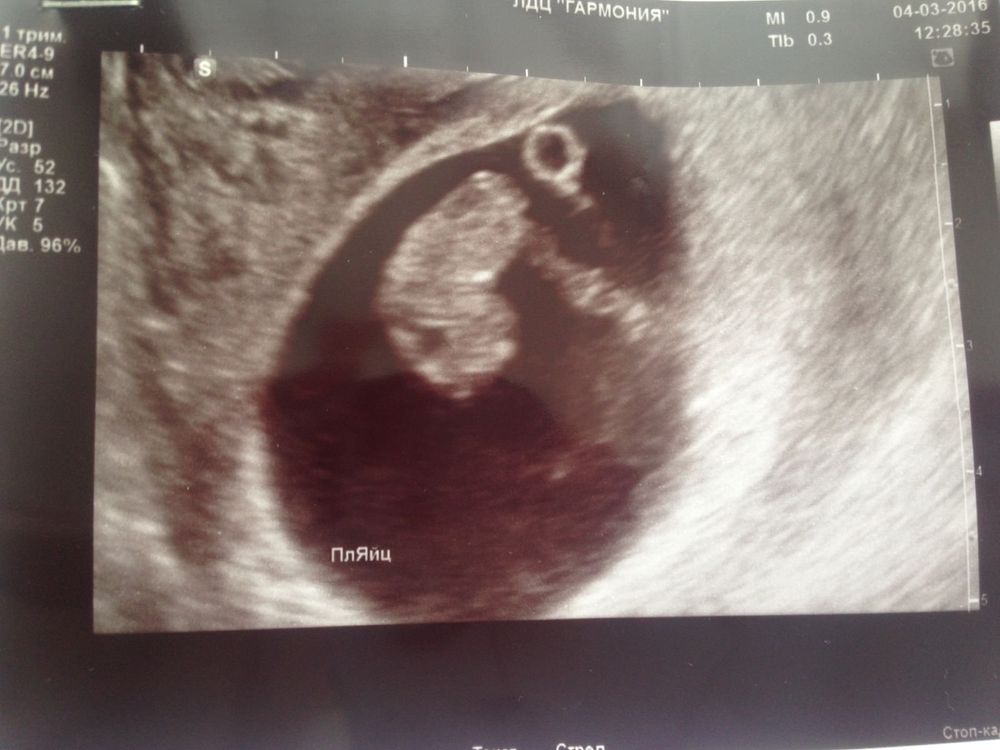

Была сегодня на УЗИ УЗИстка сказала про те забудь они уйдут но есть одно но 1 развивается сердцебиение все хорошо кроме того что плодное яйцо отстаёт сказала если будет мазать или пропадет токсикоз сразу иди на УЗИ не жди теперь у меня ещё одна фобия которую я итак боюсь и так пережила зб ещё и это 🙏 надеюсь что все хорошо будет на счёт остальных 2 тишина она на них не обращала внимания говорит они тебе не нужны

У вас ещё желточный мешочек не визуализируется...

у меня с дочкой пя было меньше ктр по сроку. Но не такая маленькая разница - слишком маленькое пя для такого ктр. Да ещё и мешочка нет...

Елена Хасап, увидела предыдущее УЗИ, хорошо что мешочек был. если его совсем не было бы, то это плохо.

Но то что он рассосался раньше времени тоже не есть хорошо, тут 50/50. Желточный мешок должен пропадать к 1 скриннингу. Это его питательный мешок, который потом в кишечник преобразуется.

Странно что вам с пя 29 поставили 7 недель,это пя соответствует 8+2,а эмбрион на 8+4 т.е все +- по сроку и то и другое,у меня пя 28,ктр 18 мм и никто ничего не говорил,что пя маленькое,по таблице мое пя на 8+1,а эмбрион на 8+2

Елена Хасап, я не вижу что свд прям маленькое по сравнению с ктр тем более если абдоминальное узи было разница в 1см почти. Нормально считию и со сроком не согласна)) мне с свд 31 поставили 7-8 недель уже никак не 7 ровно

Это УЗИ 16 октября

Вот такой шарик

Это вот первое самое УЗИ